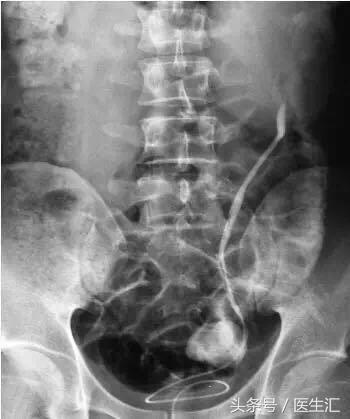

影像学检查:泌尿系平片(KUB)+静脉肾盂造影(IVP)。

KUB:双肾影清晰,双肾区、输尿管走行区及膀胱未见异常。

IVP:静脉注入造影剂5分钟、10分钟后,右肾盂呈壶腹形,杯口清晰锐利,未见明显充盈缺损及龛影,左侧肾盂肾盏扩张,肾盏杯口变平;松解压迫带后右侧输尿管通畅,左侧输尿管显影不清。右侧壶腹型肾盂,左肾积水。

逆行肾盂造影:左输尿管20cm处受阻无法通过(图4-1)。